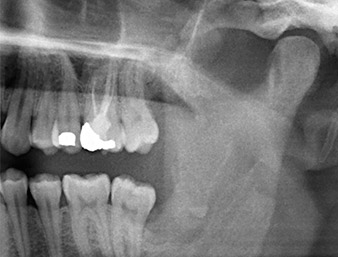

À l’OPG, le reste radiculaire dans la région de la dent 38 (LL8) apparaît déjà très proche du nerf alvéolaire inférieur. La racine s’est fracturée pendant l’ostéotomie mais n'a pas été extraite par le prestataire de soins primaires en raison de douleurs peropératoires. Pour minimiser le traumatisme causé aux tissus, la nouvelle ostéotomie devait être réalisée par piézochirurgie. Le patient ne présente pas d’antécédents médicaux particuliers et est non-fumeur.

OPG 6 mois après l’ostéotomie

Fig. 1 : OPG 6 mois après l’ostéotomie de la dent 38 (LL8) : la racine résiduelle est proche du nerf alvéolaire inférieur.

On voit sur l’image 3D (tomographie volumétrique numérique) que le reste radiculaire est en position disto-caudale au niveau de la transition de la partie horizontale vers la partie ascendante de la mandibule (Fig. 2).